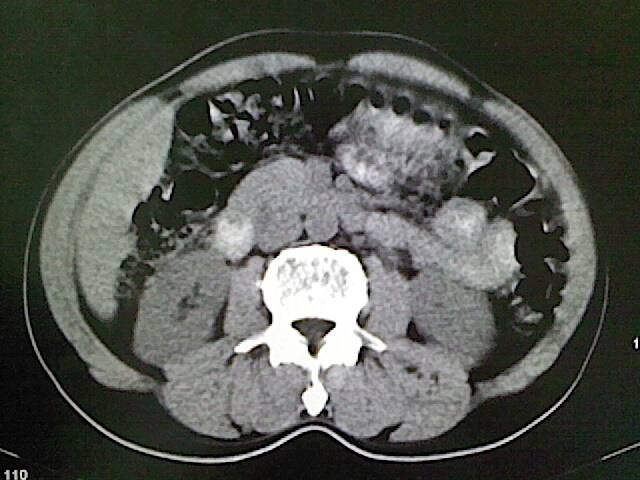

标题: CT18630:男,54岁,乙肝,大家看怎么样? [打印本页]

男,54岁,乙肝,大家看怎么样?

肝脏的要有增强敢说话

未见明确异常;建议必要时行ct增强扫描检查。

强化再讨论